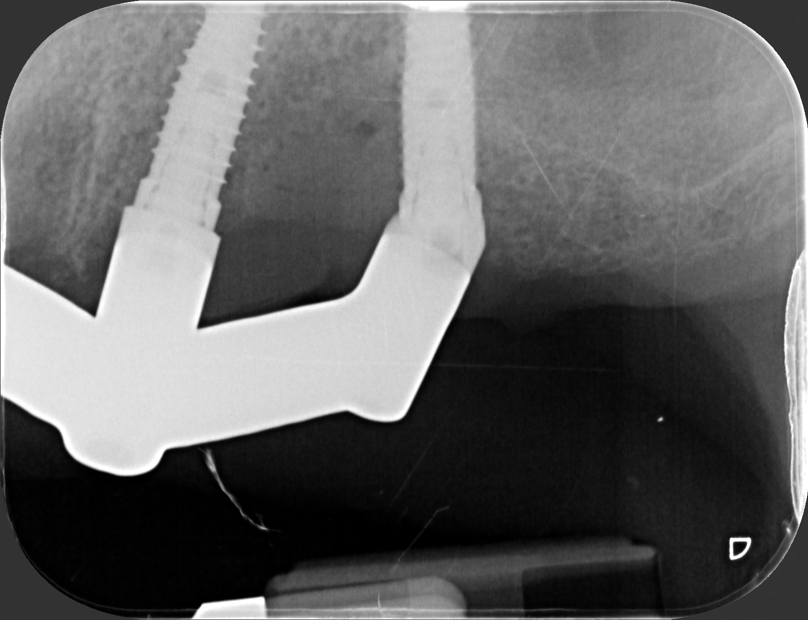

The prosthesis was also delivered 24 hours after surgery (Pic. 8), and after one week the titanium bar was tested with the “Sheffield test” (Pics. 9-11).

Fig 10

Fig 11

Due to its greater radiolucency, titanium allows for even better assessment of the bar’s fit on the angled abutments.